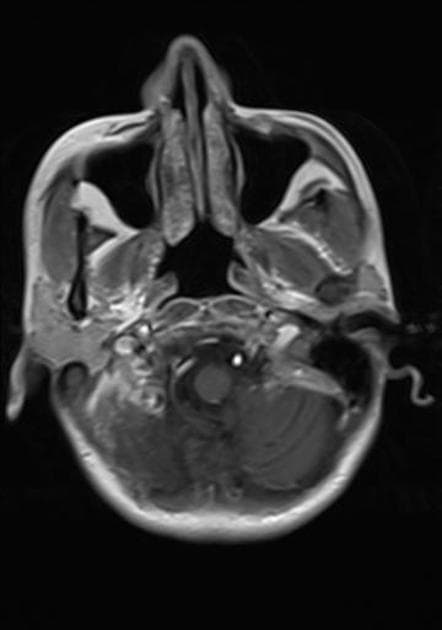

- Khối bắt thuốc dạng viền (ring-enhancing mass) ở thuỳ trán sau bên trái, kèm theo một lượng nhỏ phù vận mạch (vasogenic edema) xung quanh.

- Có một phần hạn chế khuếch tán (diffusion restriction) ở vùng ngoại vi, nhưng không có ở trung tâm.

Lesion "hoàn hảo" bắt thuốc dạng viền, nhưng không phải là áp xe não (do không có hạn chế khuếch tán ở trung tâm trên hình ảnh khuếch tán – DWI và lượng phù tương đối ít). MAGIC DR là từ viết tắt gợi nhớ hữu ích cho hình ảnh này.